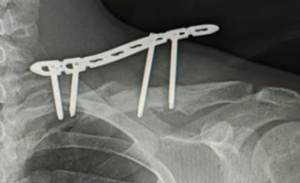

On examination, the bolts were deeply impacted in the fingers, with surrounding edema, erythema, soft-tissue involvement, and signs of early localized infection. The patient was febrile but hemodynamically stable. Radiographs confirmed a deeply embedded metallic bolt traversing the soft tissues without obvious bony involvement (Fig. 2).

Figure 2: Plain radiographs of the left hand (anteroposterior, oblique, and lateral views) showing metallic bolt-like foreign bodies tightly encircling proximal phalanges of index and ring fingers.